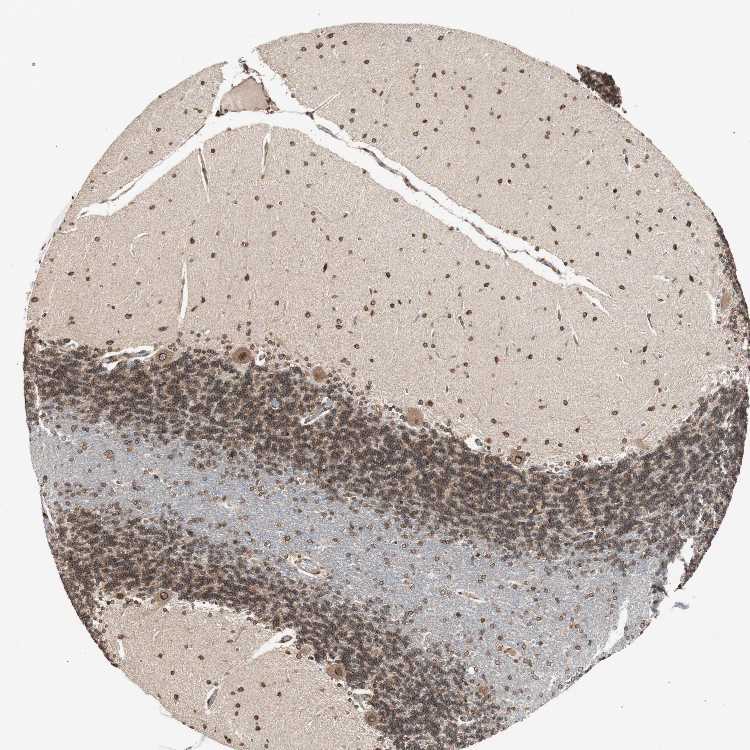

BRAIN CEREBELLUM Show tissue menu

CEREBELLUM - Expression summary

CEREBELLUM - Antibody stainingi

Antibody staining in the annotated cell types in the current human tissue is reported as not detected, low, medium, or high, based on conventional immunohistochemistry profiling in selected tissues. This score is based on the combination of the staining intensity and fraction of stained cells.

Each image is clickable and will lead to virtual microscopy that enables deeper exploration of all samples and also displays staining intensity scores, fraction scores and subcellular localization as well as patient and tissue information for each sample.

Antibody HPA005435Antibody CAB020724

Purkinje cells HighMedium

Cells in granular layer HighLow

Cells in molecular layer HighMedium